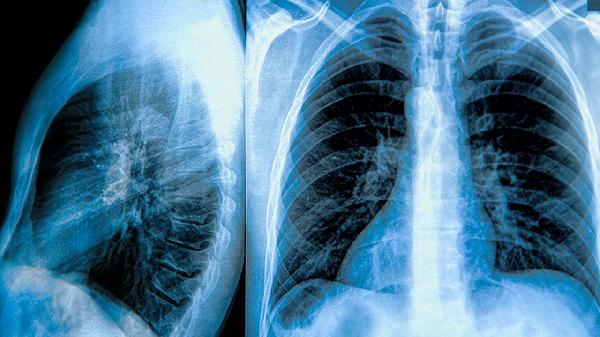

多发性肺大泡的预后取决于病情严重程度和治疗效果,及时治疗可显著延长生存期。治疗方案包括药物治疗、手术治疗和生活方式调整。药物治疗常用支气管扩张剂、糖皮质激素和抗生素;手术治疗可采用肺大泡切除术、肺减容术和肺移植;生活方式调整包括戒烟、适度运动和健康饮食。

1药物治疗是多发性肺大泡的基础治疗手段。支气管扩张剂如沙美特罗、福莫特罗可缓解气道痉挛,改善呼吸困难;糖皮质激素如泼尼松、布地奈德可减轻炎症反应;抗生素如阿莫西林、左氧氟沙星用于预防和治疗肺部感染。

2手术治疗适用于严重病例。肺大泡切除术可切除病变组织,改善肺功能;肺减容术通过切除部分肺组织,减少胸腔容积,提高剩余肺组织的通气效率;肺移植是终末期患者的最后选择,可显著改善生活质量和延长生存期。

3生活方式调整对病情控制至关重要。戒烟是首要措施,可减缓病情进展;适度运动如散步、太极拳可增强肺功能;健康饮食应富含蛋白质、维生素和矿物质,避免高脂高糖食物,维持理想体重。

多发性肺大泡患者需长期随访,定期进行肺功能检查和影像学评估,及时调整治疗方案。通过规范治疗和良好生活习惯,大多数患者可获得较长的生存期和较好的生活质量。患者应积极配合医生治疗,保持乐观心态,避免过度劳累和情绪波动,定期复查,及时处理并发症,以提高整体预后。